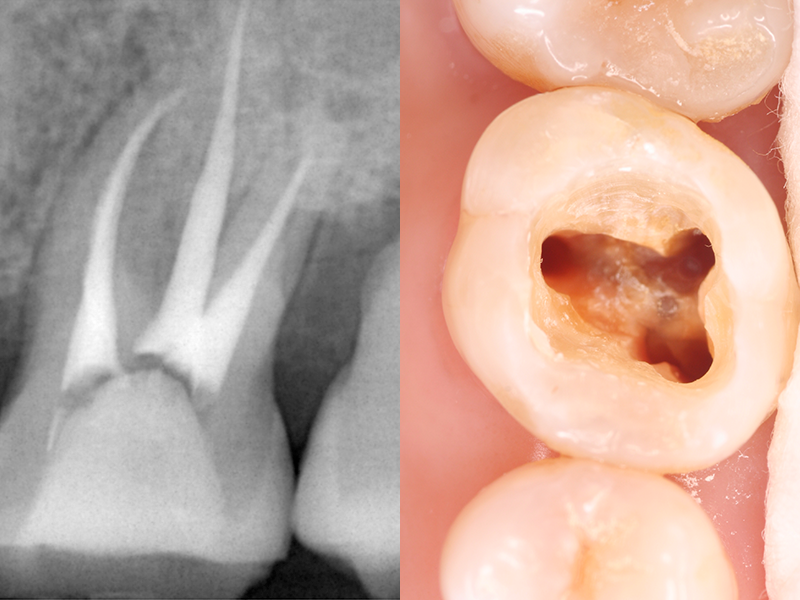

歯の内部には「歯髄(しずい)」と呼ばれる神経や血管を含む組織があります。むし歯の進行や外傷によって、歯髄が細菌に感染したり、壊死したりした場合には、歯髄を除去するための「根管治療」が必要です。

感染した歯髄や血管をそのまま放置してしまうと、炎症が広がり、抜歯のリスクが高まります。根管治療では感染した部分を丁寧に取り除き、消毒を行うことで、歯を抜かずに残せる可能性が高まります。

根管治療とは、細菌によって汚染された歯の根の内部を細い器具(ファイル)で丁寧に除去し、洗浄・消毒を行うことで、根管内の痛みや炎症を抑える治療です。治療後は、根管内に薬剤を充填し、かぶせ物やつめ物を装着することで、歯の機能を再び取り戻します。

むし歯病原菌に侵された根管内にある神経や血管を除去し、消毒のための薬剤を充填してから補綴物(ほてつぶつ)を装着することで、歯根を残す治療方法です。